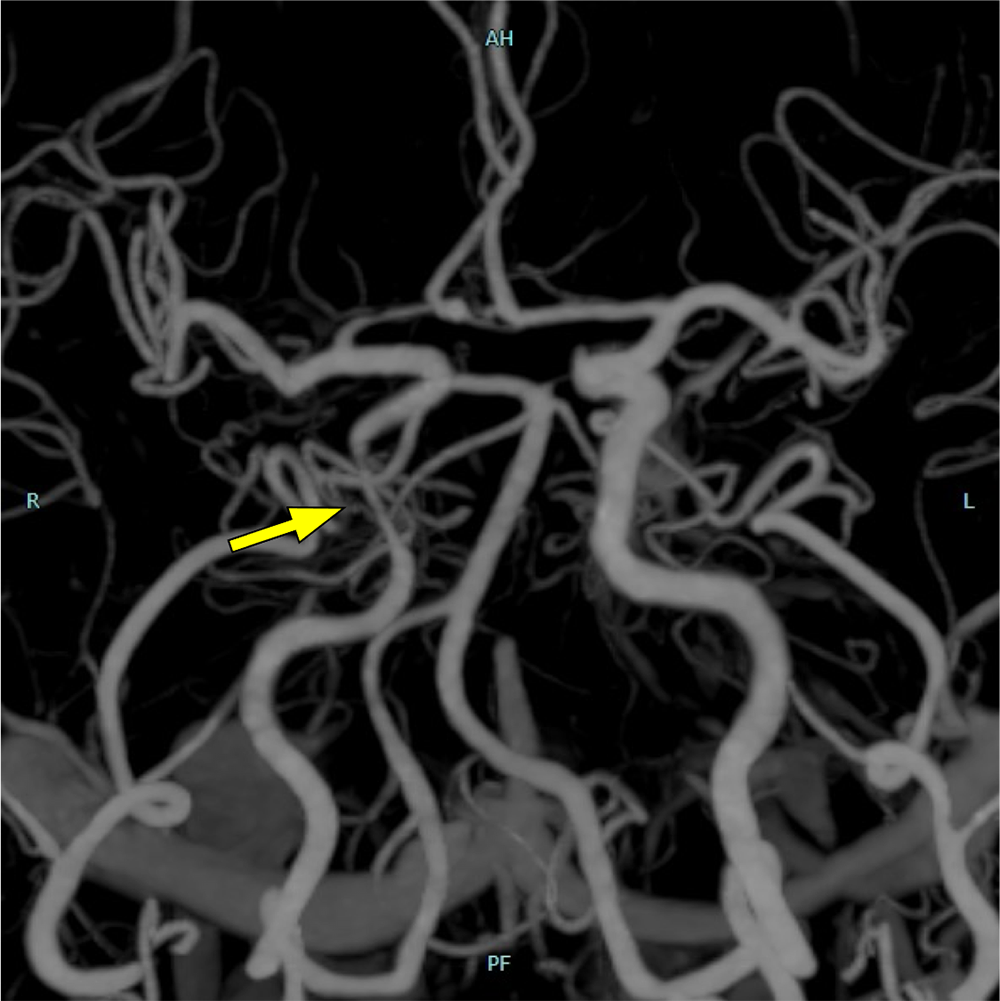

図4.3D-CTA

右内頚動脈の海綿静脈洞部に狭窄を認める。